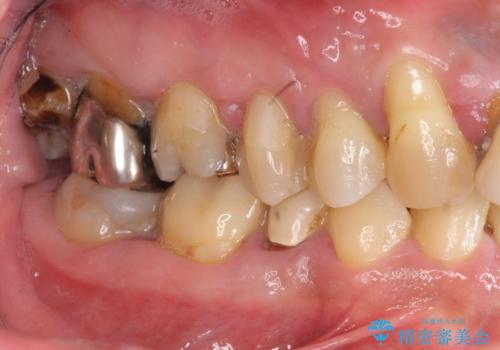

全体的な歯周病検査を行い、多数の残すことのできない抜歯の必要な歯を認めたため、残せる歯に対しての徹底的な歯周病治療、失った歯に対しブリッジ・インプラント治療を全顎的に行っていくこととしました。

長期間にわたる治療後、歯に対する意識も大きく変わりプラークコントロールも非常に良くなりました。

数ヶ月に一度のチェックをしっかりと行い、ブリッジ・インプラントが長期間使用できるようメンテンスを行っていきます。